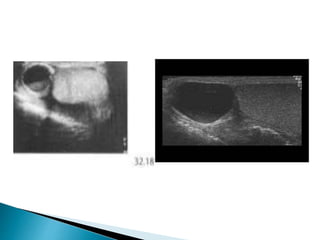

 Blunt scrotal trauma commonly results in

hemorrhage around the testicle (haematocele)

and intratesticular hematoma,

 May be associated with a tear of the tunica

albuginea.

 The commonest finding is a complex

haemorrhagic hydrocele (haematocele)

 The underlying testicle may show areas of

contusion or haematoma, visible as echo-

poor areas, often with a relatively linear

configuration.

 The testicle may be deformed by subcapsular

haemorrhage.

 There may be rupture of the capsule (tunica

albuginca ) with disruption of the underlying

testicle and associated haematoma .

 The testicular tear may be linear or complex,

 May be fragmentation of the testicle.